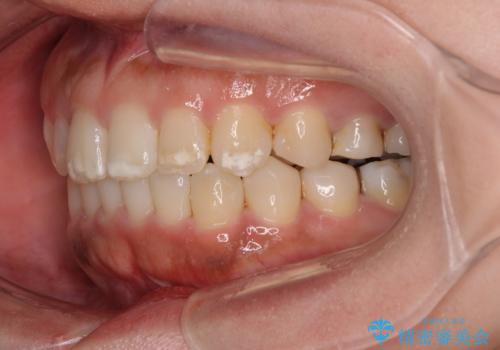

- 上下前歯の叢生を気にして来院された患者様です。

軽度な叢生であり、安価で短期間の治療を規模されていたため、インビザライン・モデレートを用いて矯正治療を行うこととしました。